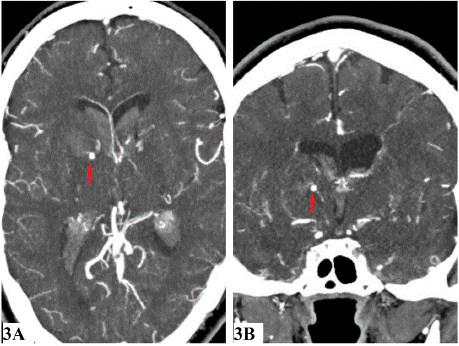

Additionally, a small focal contrast-filled outpouching was seen in the right basal ganglia adjacent to the hematoma (Figure 3). Based on these imaging findings, a diagnosis of Moyamoya disease with a pseudoaneurysm in the right basal ganglia was made. The patient was admitted for further management.

Figure 3: Axial (3A) and Coronal (3B) images showing an aneurysm in right

basal ganglia (red arrows).